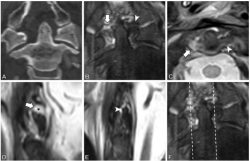

(A) Coronal noncontrast CT reconstruction in a 57-year-old man with complete rupture of the right alar ligament with lateral atlantodental interval asymmetry. (B–D) Coronal (B), transverse (C), and sagittal (D) noncontrast T2-weighted mDIXON turbo spin-echo MRI scans show rupture. Arrow indicates the ruptured right alar ligament; arrowhead in B and C shows the intact left alar ligament. Note the missing right alar ligament on sagittal plane (* in D). (E) Sagittal noncontrast T2-weighted mDIXON turbo spin-echo MRI scan on left side clearly shows the ligament (arrowhead). (F) Same image as in B. Dashed lines show position of the sagittal planes.